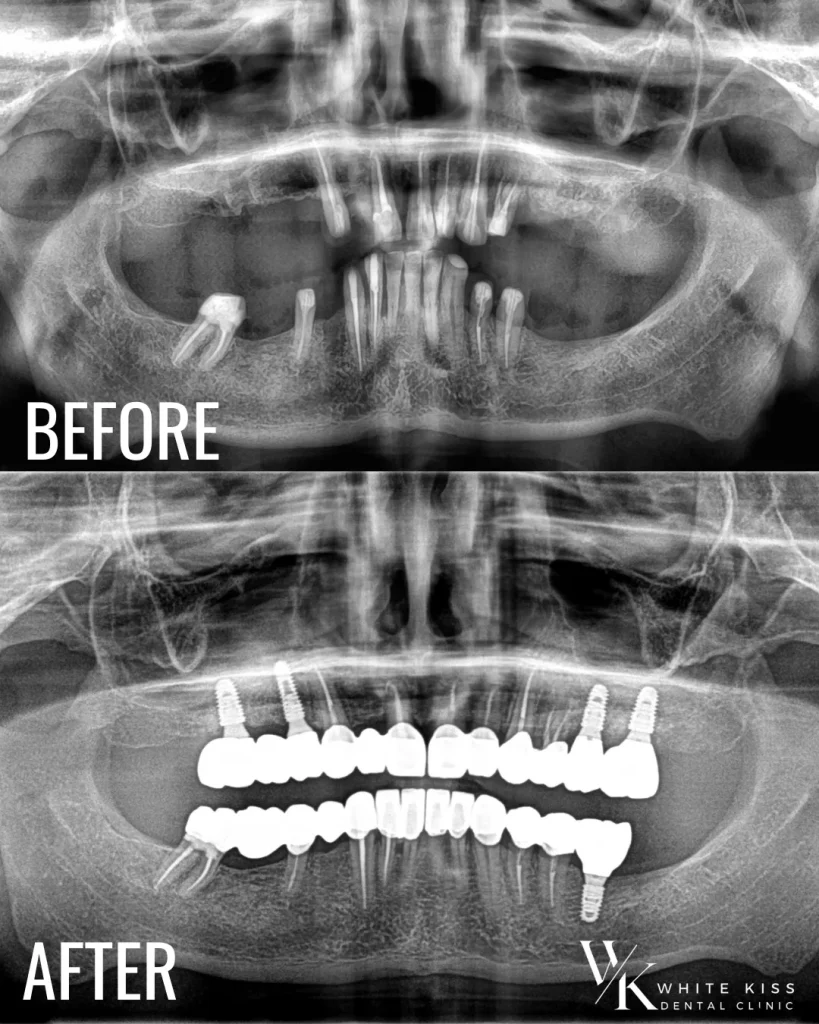

Recent, echipa WhiteKiss a avut privilegiul de a finaliza un caz remarcabil de reabilitare orală completă, care a combinat tratamentul dinților naturali restanți cu inserarea de implanturi dentare și restaurarea cu coroane premium din ceramică pe zirconiu. Acest demers complex reflectă angajamentul nostru constant față de excelență și grijă personalizată pentru fiecare pacient.

Pacientul s-a prezentat cu multiple probleme dentare, ce afectau atât funcționalitatea, cât și estetica zâmbetului. În urma unei evaluări amănunțite, echipa noastră condusă de Dr. Mircea Gheorghiță, Medic Primar în Chirurgie Oro-Maxilo-Facială, și Dr. Anca Diaconu, specialist în protetică dentară, a propus o soluție completă de reabilitare: păstrarea și tratamentul strategic al dinților viabili, completată de inserarea implanturilor acolo unde era necesar.

Coroanele din ceramică pe suport de zirconiu au fost alegerea ideală pentru acest caz, datorită combinației perfecte între rezistență, biocompatibilitate și estetică superioară. Acestea au fost personalizate pentru a se integra armonios cu trăsăturile faciale ale pacientului, oferind un rezultat natural, durabil și extrem de atrăgător.

Un rezultat de excepție nu ar fi fost posibil fără colaborarea strânsă cu laboratorul tehnic dentar Nexus. Echipa de tehnicieni a lucrat cu precizie și dedicare alături de medicii noștri pentru a realiza coroane din ceramică pe zirconiu personalizate, cu un grad ridicat de estetică și funcționalitate. Fiecare detaliu – de la nuanța perfect aleasă până la conturul natural al lucrărilor protetice – a reflectat standardele înalte de calitate ale acestui parteneriat valoros.